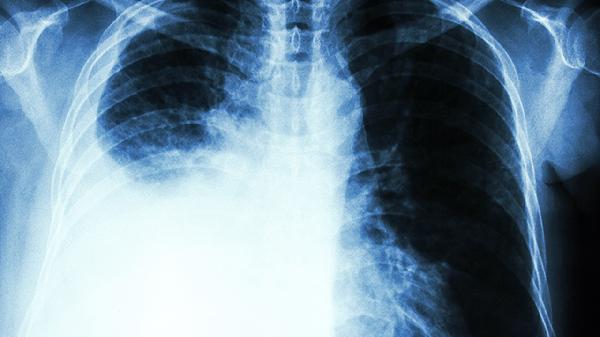

肺絮状阴影是什么病

肺絮状阴影通常是影像学描述术语,可能提示肺炎、肺结核、肺纤维化等疾病。肺絮状阴影在影像学检查中表现为肺部出现模糊的絮状或云絮样密度增高影,主要与感染性病变、非感染性炎症、肿瘤性病变等因素有关,需结合临床表现和其他检查进一步明确诊断。